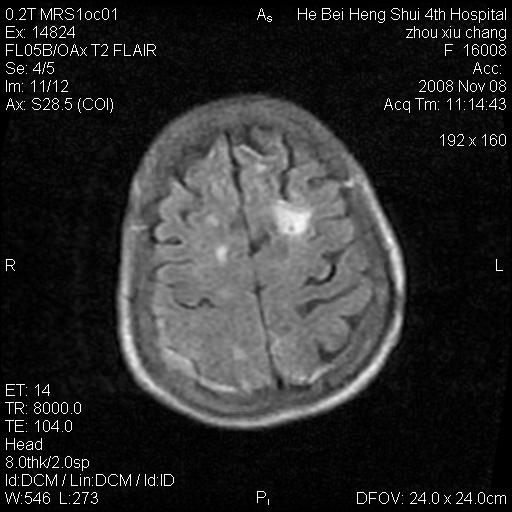

标题: MRI1883:女67岁,半年前曾患脑梗塞,治疗后好转,近3各月精 [打印本页]

女67岁,半年前曾患脑梗塞,治疗后好转,近3各月精神恍惚。

两种可能:1,转移瘤,2,脑炎,建议增强扫描

形态及整体病灶看起来首先考虑转移瘤或淋巴瘤,但奇怪的是多个病灶周围均未见显著的水肿区,这不符合这两个肿瘤的特点,结合ct表现及患者病史有个人考虑是否有皮层下动脉硬化性脑病伴多发胶质增生可能.